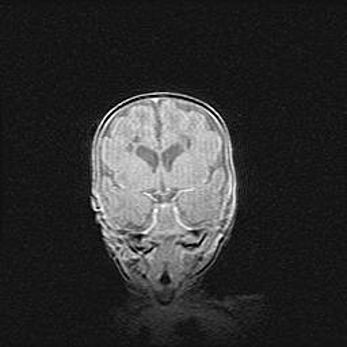

Открытая гидроцефалия.

Возраст: 6 месяцев 15 дней

Вес: 6200 г

Пол: женский

Окружность головы: 41 см

Срок гестации: 38 недель

Гидроцефалия головного мозга у новорожденных – это скопление избыточного количества цереброспинальной жидкости в головном мозге. Ее избыточное скопление в мозге приводит к патологическому расширению желудочков мозга (четырех полостей, расположенных в глубине белого вещества мозга, заполненных цереброспинальной жидкостью и связанных узкими проходами).

Открытый тип гидроцефалии (сообщающаяся) наблюдается тогда, когда нарушен механизм всасывания ликвора в системный кровоток. При этом типе причиной заболевания чаще всего является перенесенные ранее инфекции (например: менингит),  либо же наличие крови в субарахноидальном пространстве.